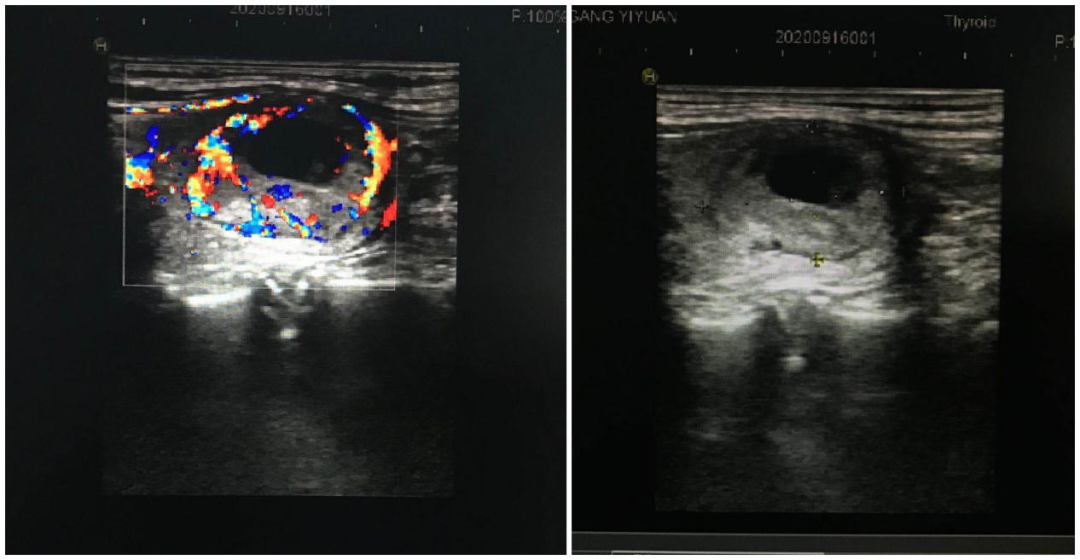

甲状腺结节的良性与恶性?

答:目前超声是甲状腺结节的首选检查,最最可靠的方法是超声图像引导下细针穿刺活检,进行病理学检查,确诊结节是良性还是恶性的。